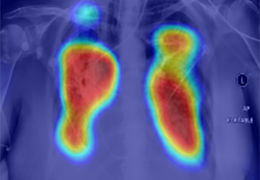

成像智能。

Eclipse 成像智能功能提供强大的处理能力和最佳质量的影像,同时减少质量错误并提高剂量效率。

凭借 AI、专有算法和先进的影像处理能力,提供出色的影像质量和无与伦比的诊断信心。

与标准影像处理相比,智能降噪功能可使客户降低辐射剂量,而不会损失影像质量。这在新生儿和儿科成像中尤其重要,在这种情况下以尽可能低的剂量成像至关重要。

提供相配视图选项,以减少所需的曝光次数,并提供更清晰的感兴趣区域视图。